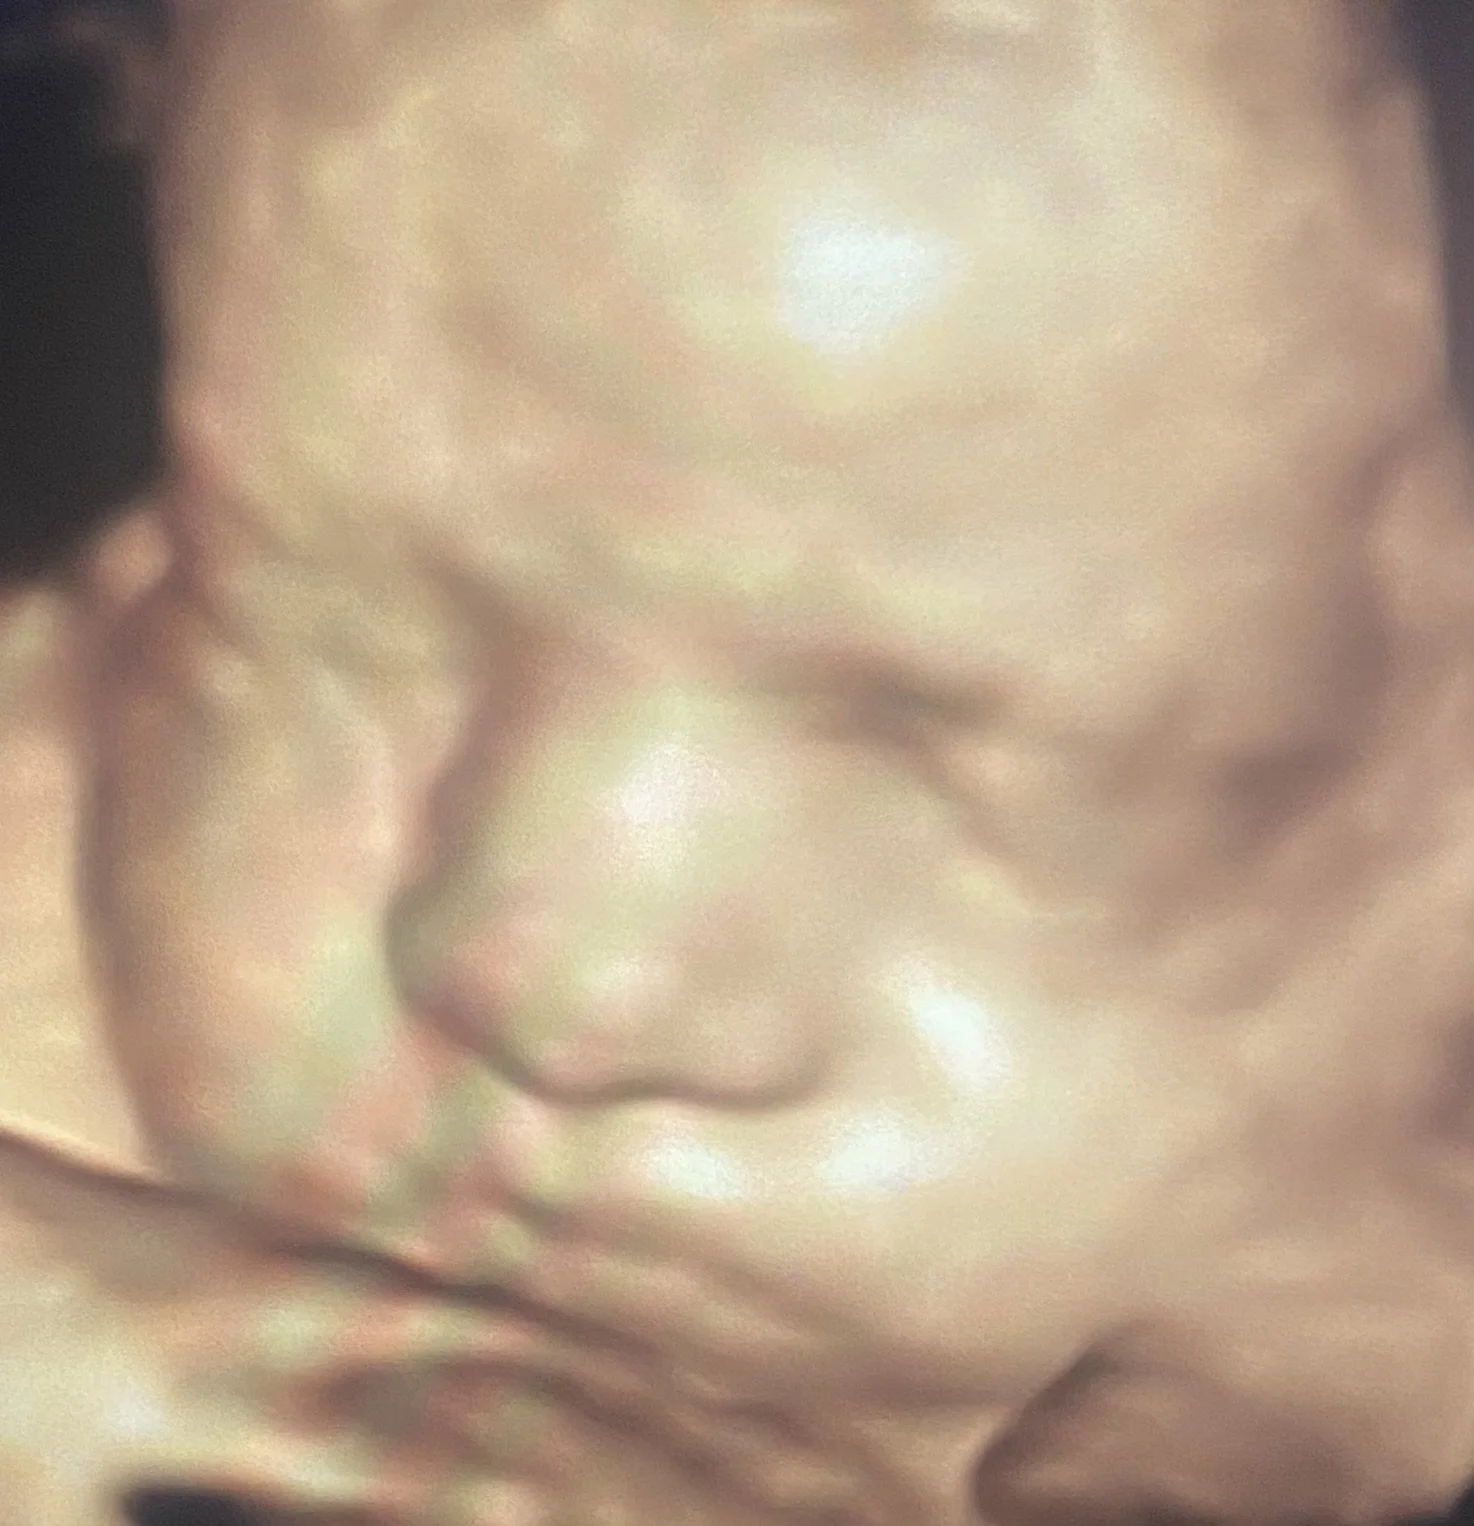

ScanSanctuary Client Scan Examples

Our state-of-the-art technology (GE Voluson Swift) is one of the most popular ultrasound machines for obstetric scanning. It features class leading 4D imaging as well as proprietary GE efficiency technologies. 3D/4D imaging modes, CrossXBeam and Speckle Reduction imaging assist with excellent accuracy.